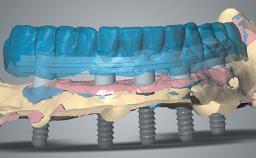

This case outlines a complex reconstruction involving use of a preconstructed fibula graft pre-installed with implants. It demonstrates the benefits of backwards planning from the desired occlusion using digital planning and 3D printing. A 43-year-old male patient was referred to the department of Oral and Maxillofacial Surgery, University Medical Center Groningen, Netherlands for secondary reconstruction of the maxilla. Twelve years previously, a hemimaxillectomy had been performed elsewhere because of a maxillary osteosarcoma. The resulting defect had been reconstructed using a deep circumflex iliac-artery flap and radial forearm flap.